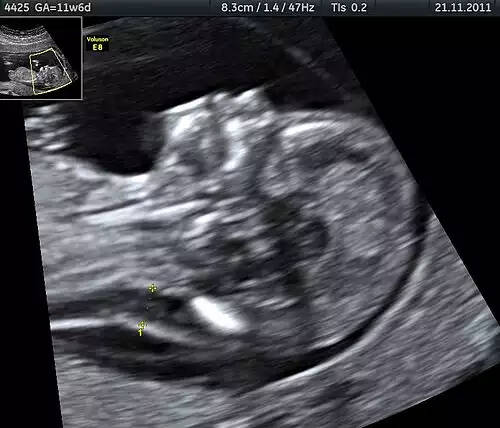

مرده زایی ( انگلیسی: Stillbirth ) به مرگ نوزاد جنین بعد از هفته بیستم بارداری گفته می شود. در این حالت ممکن است به عمل سزارین نیاز شود. اکثر مرده زایی ها در انتهای دوره بارداری رخ می دهند و در اغلب موارد علت اصلی آن مشخص نیست. مرده زایی را نباید با سقط خودبه خودی، که از دست دادن زودرس نوزاد است، اشتباه گرفت.

به دنیاآوردن نوزاد مرده، پس از هفتۀ ۲۴ حاملگی. پیش از این زمان، مرگ جنین سقطنامیده می شود.